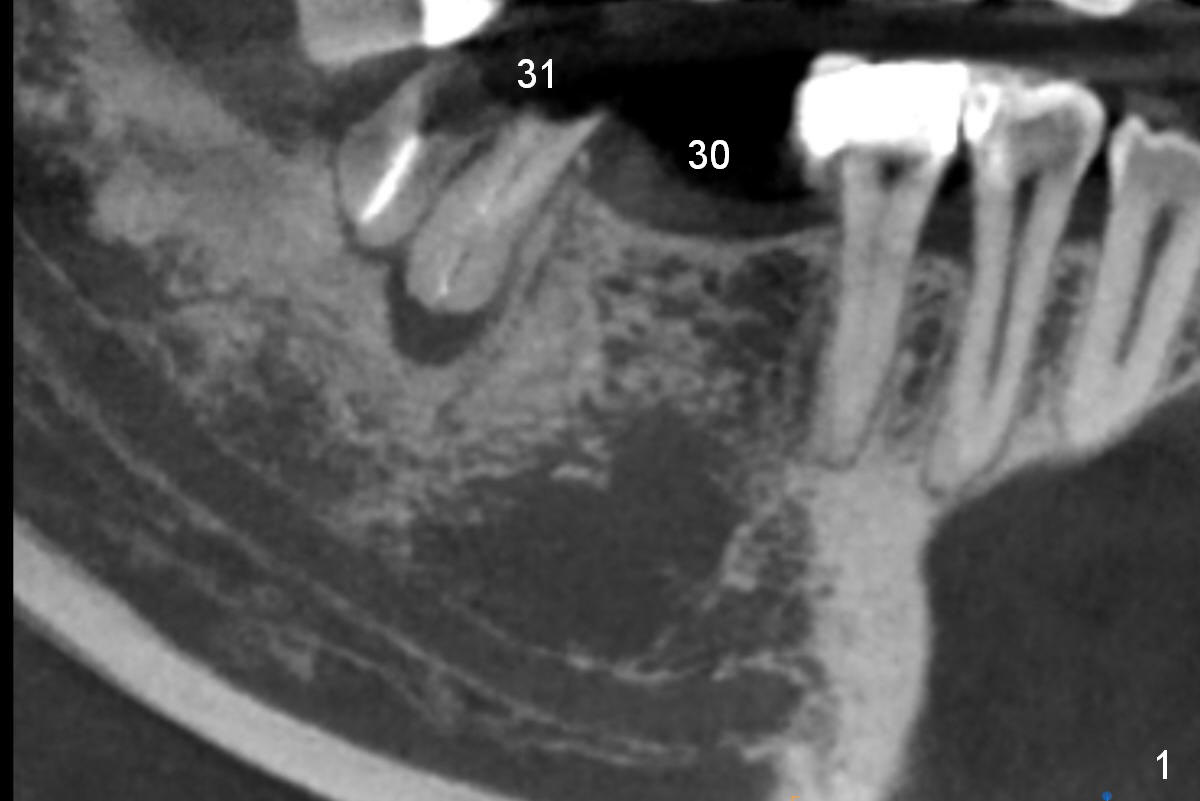

A 47-year-old woman has had 3 bridges. One of them (the lower right) is broken down. The patient requests removing the tooth #31 (Fig.1 CBCT), because of difficulty in keeping it clean. Since the buccal plate is thin (Fig.2 (axial section), 3 (coronal section) >) or absent (Fig.2 *), a 5 mm implant will be placed lingually (Clindamycin). Tap will be used prior to implant placement.